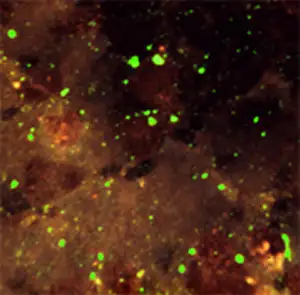

直接荧光抗体法是生前诊断最常用的方法。医生会从患者颈后部取一小块皮肤活检样本,用荧光标记的抗狂犬病毒抗体染色。如果存在病毒感染,在荧光显微镜下会看到特异性的苹果绿色荧光。这种方法的敏感性和特异性都很高,但需要在专门的实验室进行。

直接免疫荧光法诊断狂犬病。这张图片来自1965年一只狂犬狐狸的脑干印片,使用荧光标记的抗狂犬病抗体染色。这种方法自1958年首次应用以来,至今仍是狂犬病诊断的金标准。